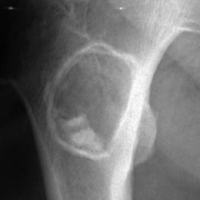

Aspect typique : Lésion lytique, de densité ou de signal graisseux, centro-osseuse au niveau de la région métaphysaire des os longs, de la région sous trochantérienne ou du calcanéum et contenant une calcification centrale

Aspect Radiologique :

- ostéolyse, bien limitée de 3 à 6 cm de diamètre

- contient souvent des trabéculations conférant un aspect cloisonné à la lésion

- entourée d'un fin liseré de condensation (type IA1) complet ou incomplet

- peut souffler la corticale (côtes) et contient dans prés de la moitié des cas une calcification centrale (typiquement au niveau du calcanéum) ou une ossification centrale  par nécrose graisseuse

- pas d'érosion corticale ni de réaction périostée